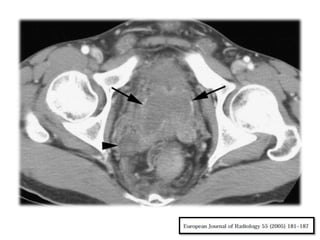

Vejiga

Los cambios tempranos en la vejiga

generalmente se desarrollan alrededor de los

orificios ureterales.

Se produce un engrosamiento de sus

paredes, ocasionalmente se encuentran

pequeñas calcificaciones.

Es frecuente encontrar defectos del llenado

vesical que son confundidos con carcinomas de

células de transición.

Los cambios inflamatorios resultantes (capacidad

vesical reducida) son evidenciados en los

estudios de cistografía.